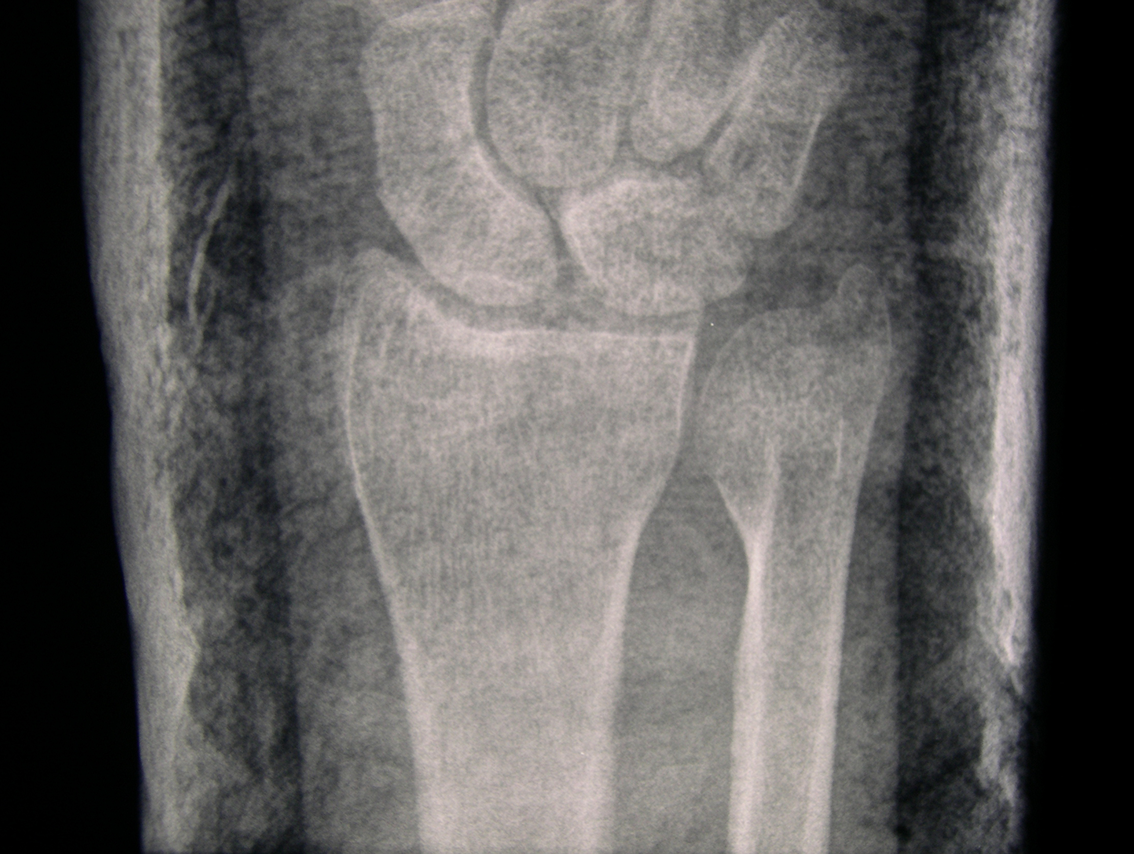

When my arm was in plaster I initially found that the plaster felt supporting because it restricted movement which had been painful. It took over the job on the outside that the bone would have done on the inside, forming an exoskeleton, and by doing so gave the bone the opportunity to heal itself. By the second week the pain had died down and I wanted to be able to move my wrist and thumb but couldn’t. As well as being supported I now felt contained in the plaster; restricted and uncomfortable. After six weeks of not moving my hand it began to ache and I really felt the restriction of not being able to clench my fist. The bones in the hand move in so many directions all of which had been immobilised in the plaster except wiggling my fingers to keep circulation. When the plaster was taken off after nine weeks my hand was rigid and completely immobile, my wrist was locked solid and all my muscles had completely wasted away leaving a bony, shrivelled, scaly, distorted object. I had been looking forward to being able to move it again but the combination of being so stiff and feeling so fragile meant that much of the restriction remained even after the plaster was removed.

Whether the cast on my arm felt supportive or restricting was dependant on the condition of the arm. When the wrist was most injured and needed support then it was a positive experience. Once healed well enough the plaster served as protection from knocks for the new soft bone but also became restrictive. Whilst the plaster supports the bones it also causes the muscle to waste and this creates a conflict between doctors and physiotherapists. The doctor is concerned with the bone rather than the movement and so can be tempted to leave the plaster on too long causing irreversible damage to movement. There is a fine line between providing support and causing damage through restriction. What I find interesting in the tension between the physiotherapist and doctors is that the latter seeks to secure a static structure in repairing the bone whereas the physiotherapist’s purpose is to help restore movement in freeing the joints and rebuilding muscle.